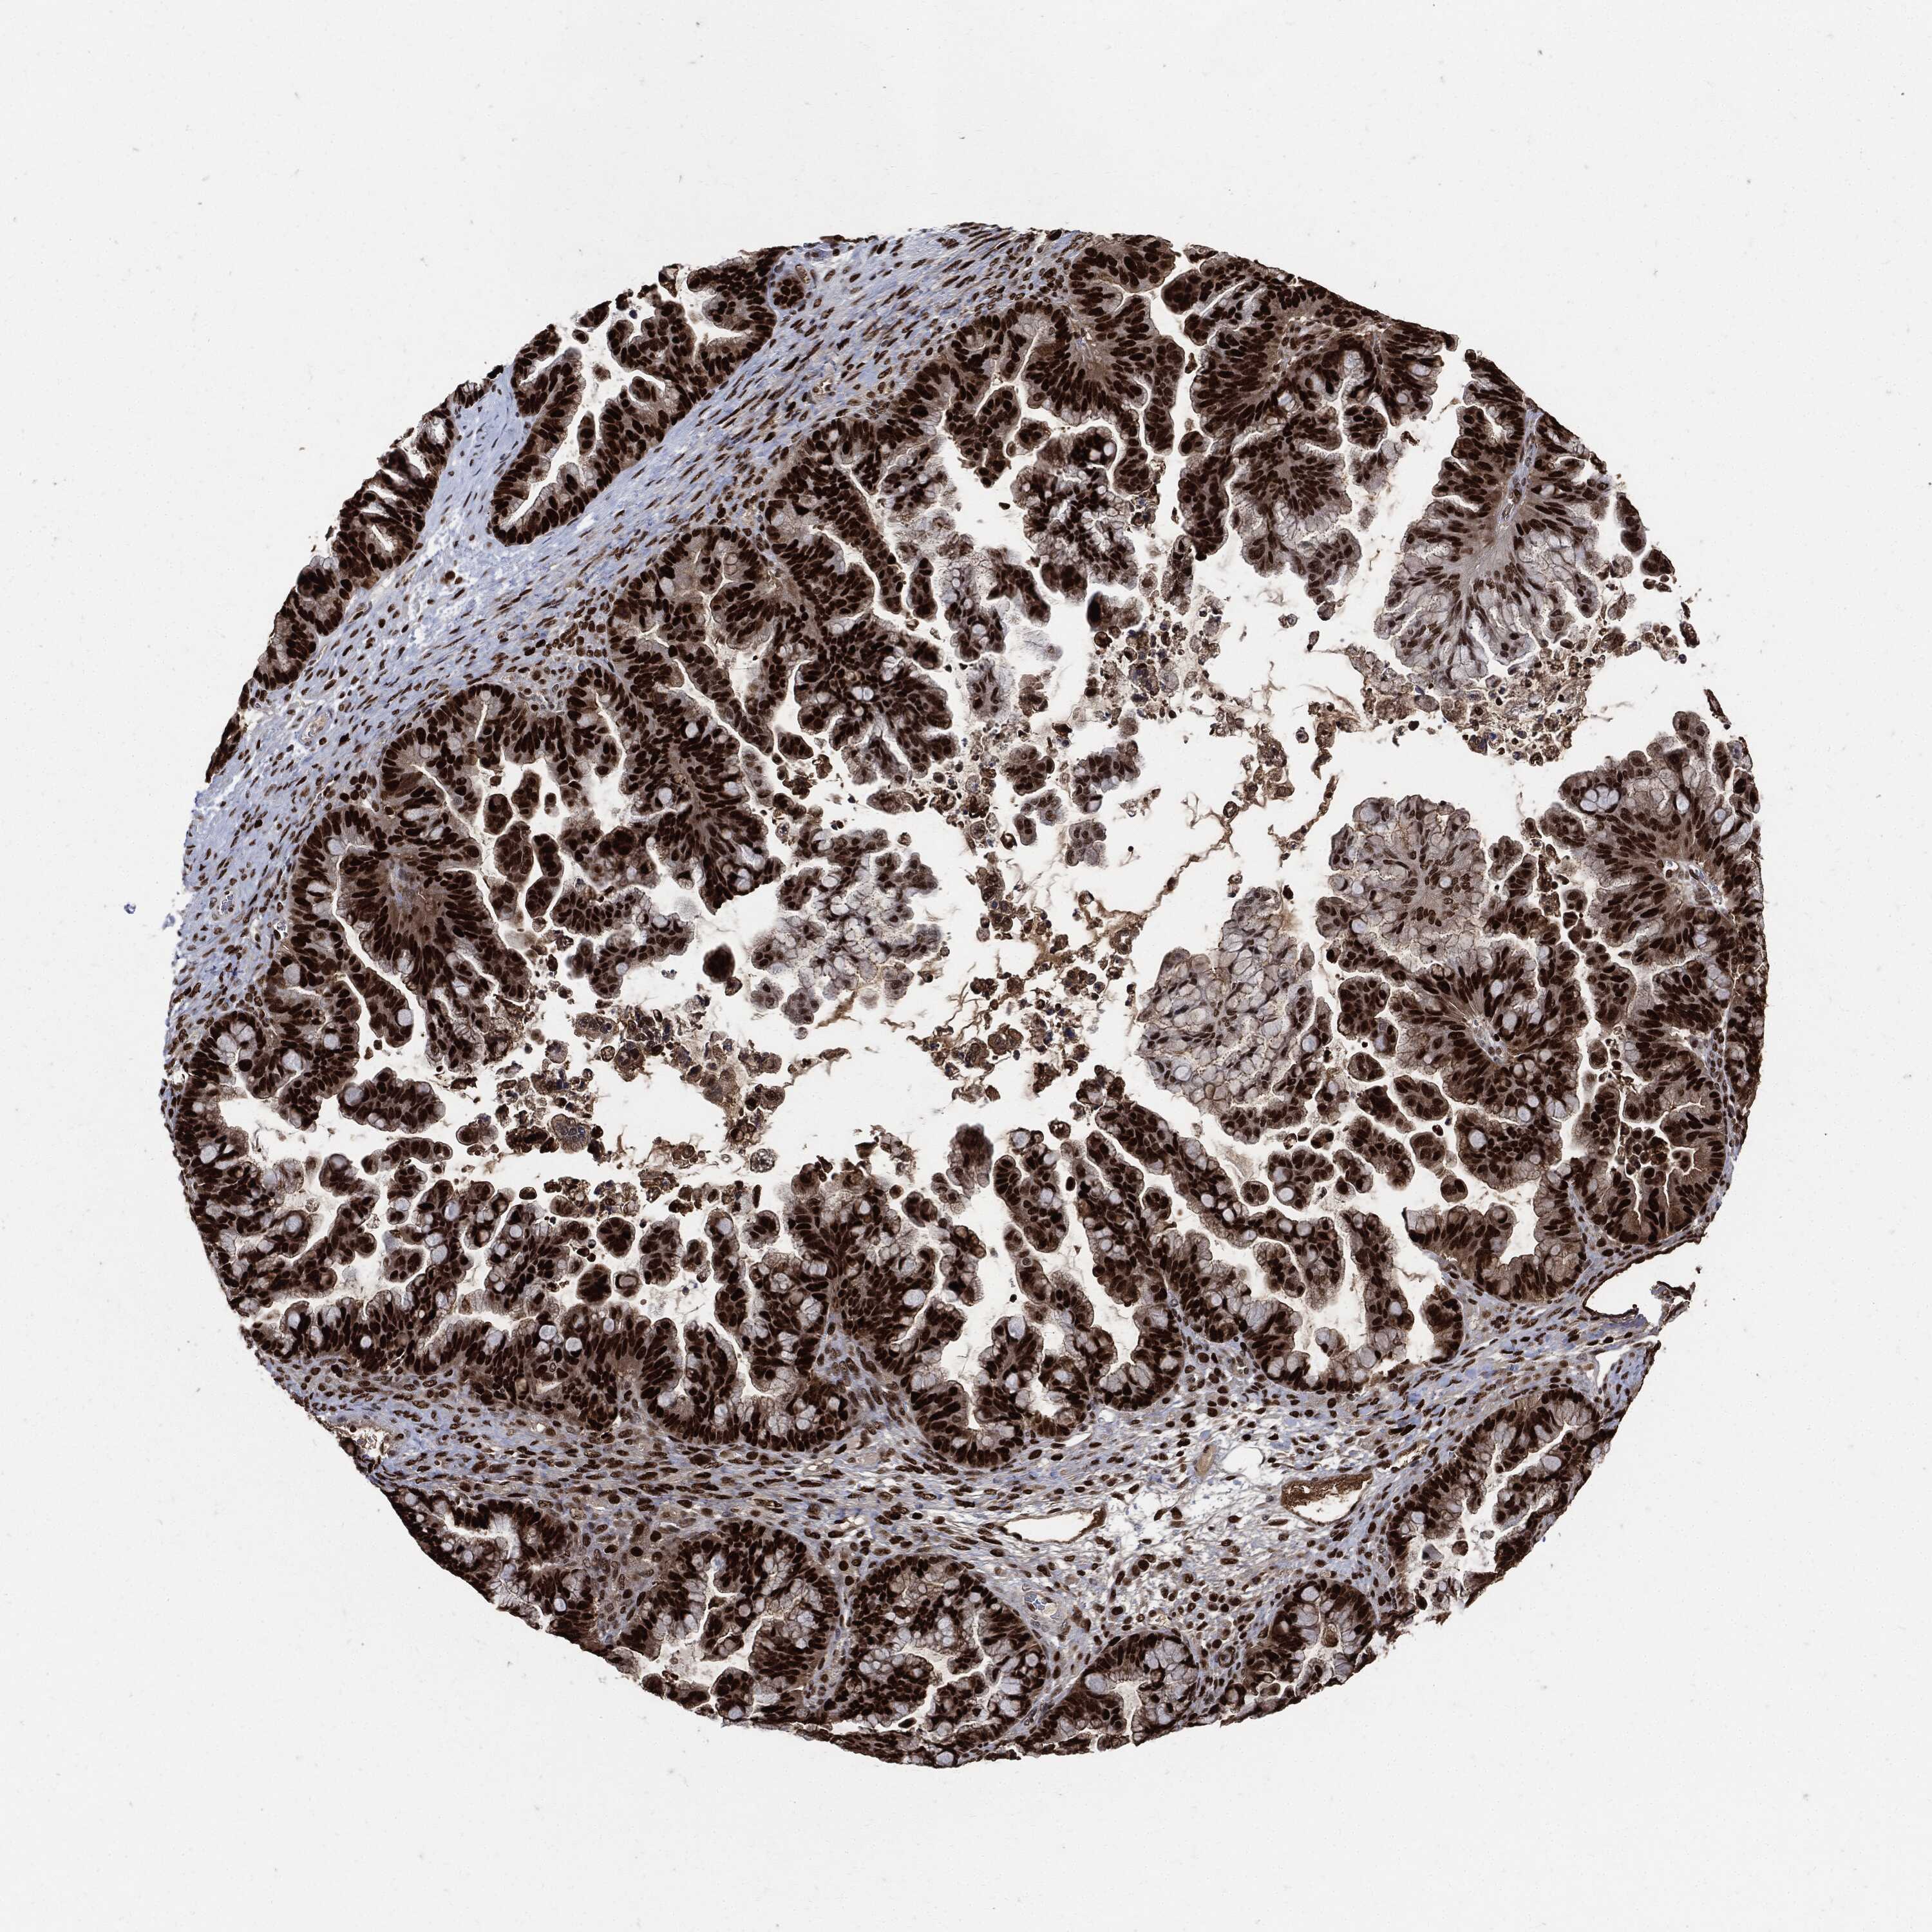

OVARIAN CANCER - Protein expressioni

A mouse-over function shows sample information and annotation data. Click on an image to view it in a full screen mode. Samples can be filtered based on level of antibody staining by selecting one or several of the following categories: high, medium, low and not detected. The assay and annotation is described here.

Note that samples used for immunohistochemistry by the Human Protein Atlas do not correspond to samples in the TCGA dataset.

Antibody stainingi

Antibody staining in the annotated cell types in the current human tissue is reported as not detected, low, medium, or high, based on conventional immunohistochemistry profiling in selected tissues. This score is based on the combination of the staining intensity and fraction of stained cells.

Each image is clickable and will lead to virtual microscopy that enables deeper exploration of all samples and also displays staining intensity scores, fraction scores and subcellular localization as well as patient and tissue information for each sample.

Cystadenocarcinoma, serous, NOS